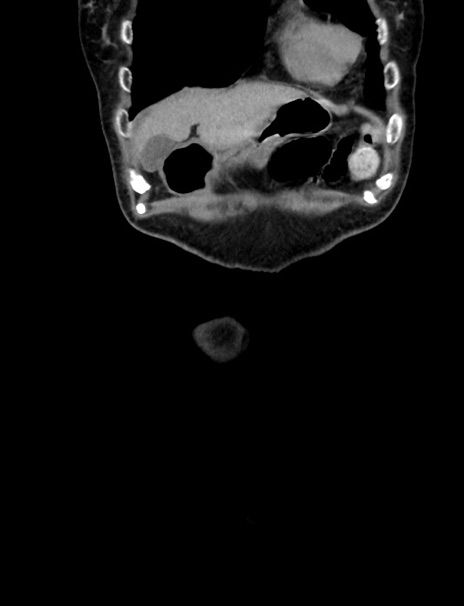

横断像